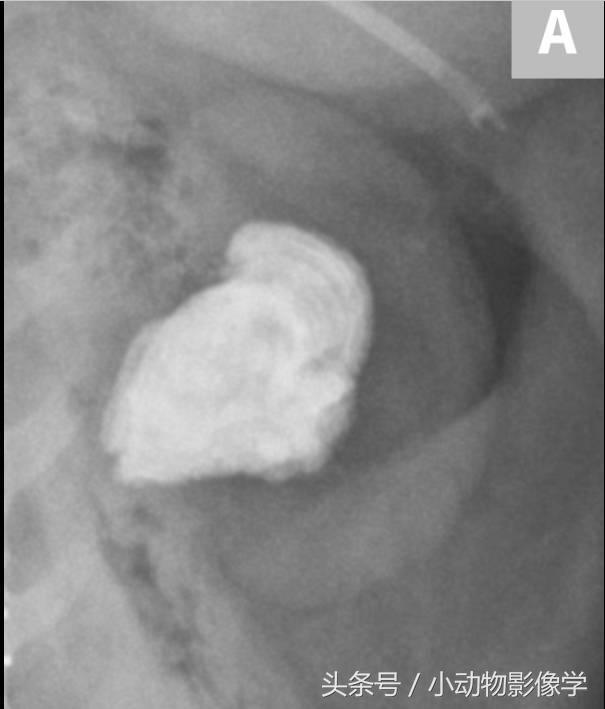

图3A、一只临床表现正常的犬X光片,这是左肾图像的特写图片,可见一个大块、边缘光滑的肾结石。

图3B、图3A中左肾的超声图像。可见结石的高回声平滑表面,和由矿化结石引起的明显的远端声影伪像(S)。